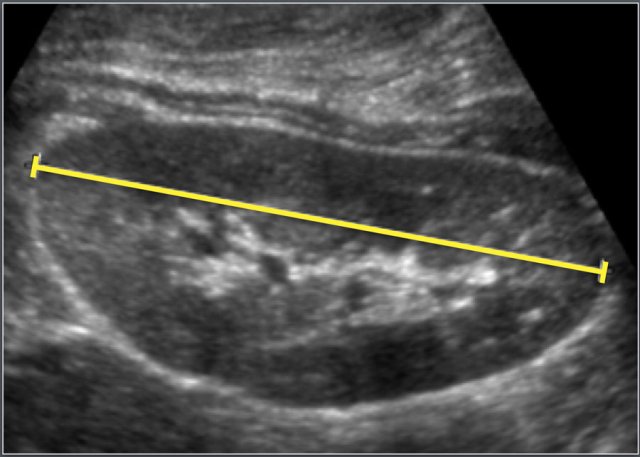

Ultrasonographic measurement of the length of a kidney.

Craniocaudal dimension of the kidneys was determined with ultrasonography.

Ultrasonographic measurement of the length of a neonatal kidney.

Note the increased echogenicity of the renal parenchyma compared to liver parenchyma.

This is normal at this age.